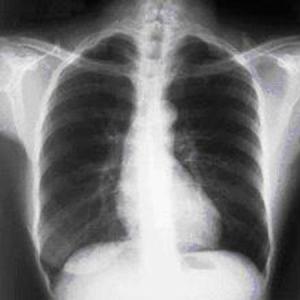

Pericardial tamponade: admission chest x-ray

Usalan C, Atalar E, Vural FK. Pericardial tamponade in a 65-year-old woman. Postgrad Med J. 1999;75:183-184; used with permission.